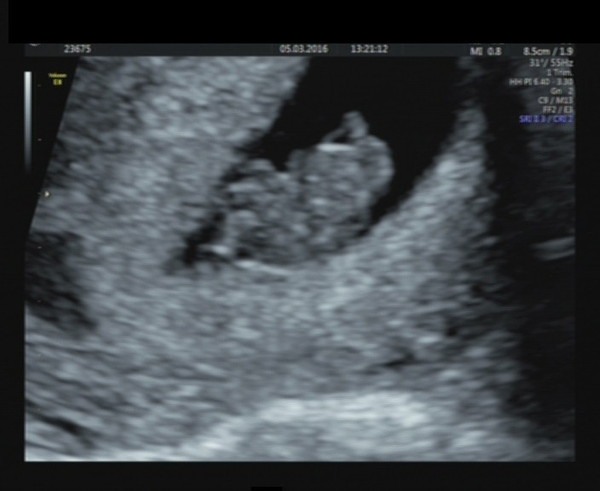

I don't think I mentioned before that I have stage IV endometriosis and only one fallopian tube - even more astonishing to be pregnant naturally this time. I had a scan this morning (37 weeks now), and it seems the baby is no longer breech, hurrah! The only half-decent picture they could get is a view right up her nose Grin